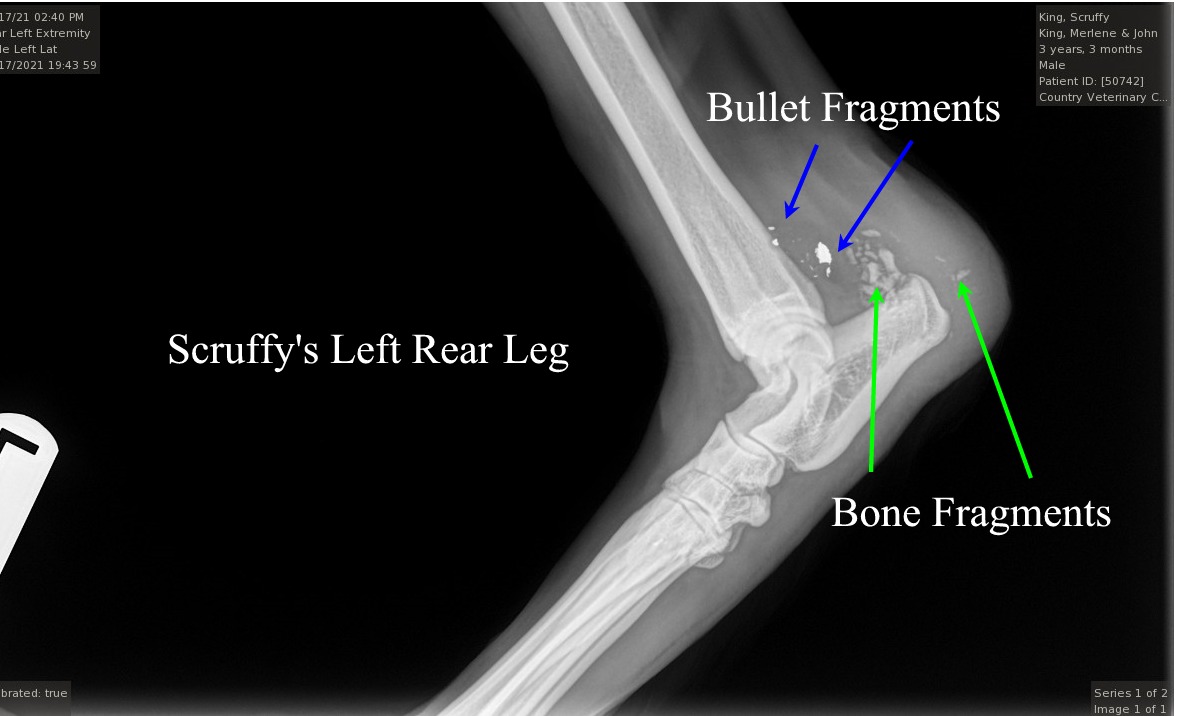

12/18/21  Scruffy is home recovering from a small caliber high velocity bullet.  Vet said 22.  My guess is a 223 and we all know this is cambered a lot for ARs.  So, we have a wannabee Rambo dog sniper someplace within a few miles of me.  Key here is all the shattered bone that's too much for a rimfire 22. Click bullet fragments X-Ray

Scruff's exit wound has closed by about 25% in a week.  Suspect .223 caliber.  Vet said it was a hollow point for blew off a chunk of his skin 1" by 2 1/4".

Just a 1/4" one way, or another would have shattered the bone completely, or cut his Achilles tendon.  Making him crippled for life. Click bullet exit 12/23/21

All good news with yesterday's visit to the vet's office with Scruffy.  Dr. Crystal McConnell decided not to open the wound to remove bone splinters and let the wound heal naturally.  More info on this tomorrow as we approach Christmas.

8:30am this morning Scruffy has an appointment with Country Vets in Ludington.  He'll, be seeing Dr. Crystal McConnell for a decision on surgical removal of bone splinters.  I hope not.  Fearing opening the gunshot wound will only make matters worse.  Overall, Scruff is doing excellent and using his shot-up leg 100% of the time.